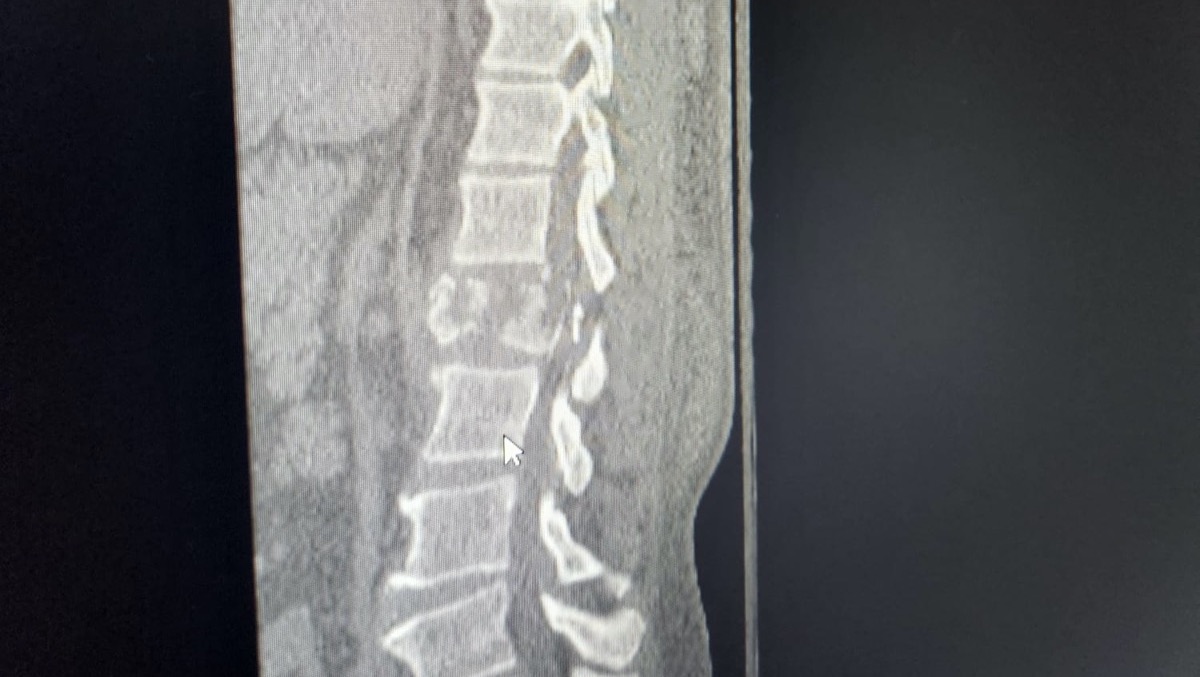

On the evening of June 8th, Raul Faife was in the backyard doing some mechanical work on a boat when he fell and broke his back, causing significant damage to his spine. Specifically his L1 vertebrae. It was completely crushed, and Drs at Jackson Ryder Trauma performed a laminectomy and a fusion (pins and rods). The surgery was successful, but Raul is now paralyzed from the waist down. We pray that Raul may walk again with healing and rehabilitation exercises. So far, he is hopeful of achieving a full recovery.